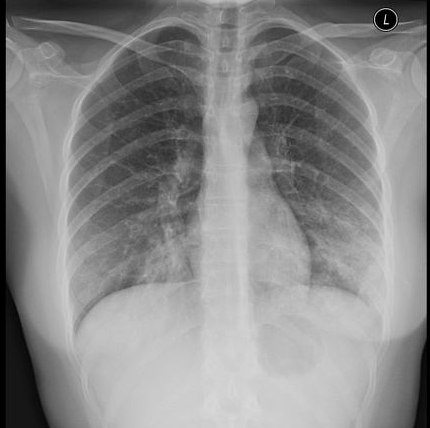

- 흉부 X-ray: 마이코플라즈마는 폐렴 소견이 약하거나 특이할 수 있어요.